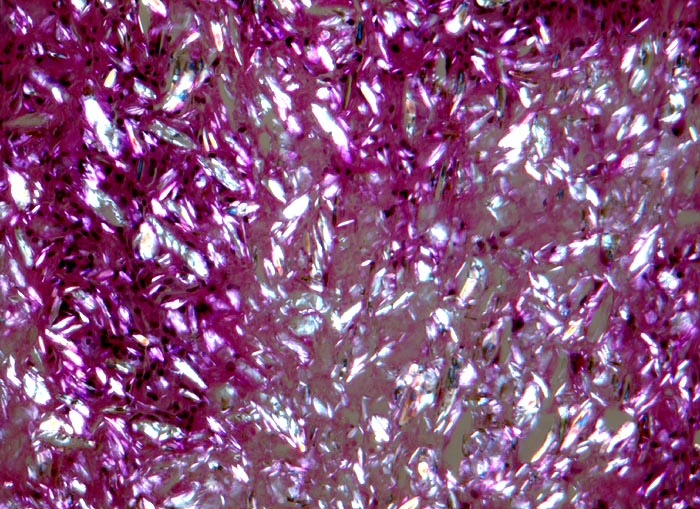

Morphologische Merkmale:

• Knotige Granulome umgeben von wenig Skelettmuskulatur.

• Granulombildung aus Histiozyten und mehrkernigen Riesenzellen vom Fremdkörpertyp.

• Im Zytoplasma der Riesenzellen findet sich phagozytiertes exogenes Fremdmaterial.

• In den helleren Arealen des Granuloms liegen grössere Ansammlungen von Fremdmaterial extrazellulär.